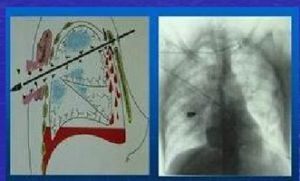

胸腹聯合傷 開放傷時子彈、彈片或刃器可經胸腔、膈肌、腹腔或以相反方向使胸腹腔臟器和膈肌均遭受損傷,在傷道經過的全程,造成多種臟器同時損傷。閉合性損傷時下胸部或上腹部突然受強力擠壓或撞擊,使胸腔或腹腔內壓力驟然增高,造成胸內或腹內臟器損傷。

胸腹聯合傷右側多於右側,雙側同時損傷者少見。胸腹聯合傷時可發生心、肺、大血管損傷,膈肌破裂,多個腹部臟器損傷,在右側常傷及肝、膽,在左側常傷及脾和胃,其次是腎、結腸、胰腺及小腸身。膈肌破裂口較大時,則發生創傷性膈肌疝,創傷性膈疝發生率以左側為高。上述損傷的結果,主要造成呼吸循環功能障礙及胸愎腔污染。受傷臟器越多,傷情越嚴重,死亡率越高。

X線檢查是胸腹聯合傷診斷鹼查的重要手段,通常可照臥位及立位胸腹部平片。胸部可觀察有無血、氣胸,肋骨骨折,胸內有腸、胃等疝入徵象時,有助於胸腹聯合傷的診斷。觀察有無膈下游離氣體.對腹腔空腔臟器破裂的診斷有較大價值。如果臥位X線檢查有胸腔積液,立位檢查積液減少或消失,應懷疑有膈肌破裂。需注意的足約30%的膈肌和腹內臟器損傷病人,無X線陽性發現。

凡外傷病人有以下情況者,應考慮胸胸腹聯合傷:①腹部傷並有呼吸困難、紫紺或縱隔移位者;②胸部外傷之後,腹部漸塌陷,胸部聽到腸鳴音者;③經胸部傷口或胸腔引流管流出消化道內容物者;④胸部X線檢查,發現腹內臟器疝入胸腔者;⑤胸部盲管傷,又有腹內臟器傷證據者。